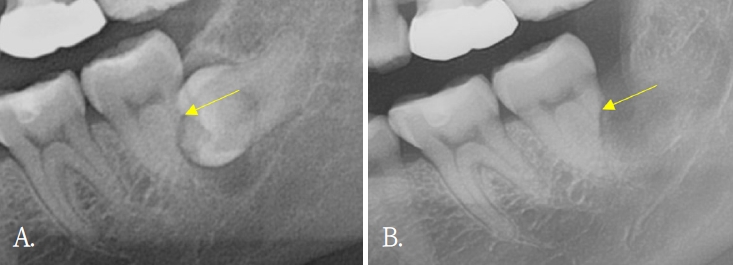

In 6 of 10 patients, dentin bridge formation and bone healing at the PRF application site were visible on panoramic radiographs (Figs. 1 and 2), excluding 4 patients who returned only once within one month postoperatively. In Table 2, patients who presented radiographic improvement and patients who had uncertain radiographic results due to insufficient follow-up period were described. In addition to bony healing, dental pulp atrophy was detected in a case (Fig. 3). No additional ERR was observed in any patients. Only one patient had preoperative and postoperative CBCT, and dentin formation and bony healing was seen on CBCT 6 months after surgery.

Pulpal atrophy with apex closure is visible on postoperative panoramic radiography (yellow arrows). A. Pre-operative panoramic radiography. B. Panoramic radiography after 4 months of surgery.